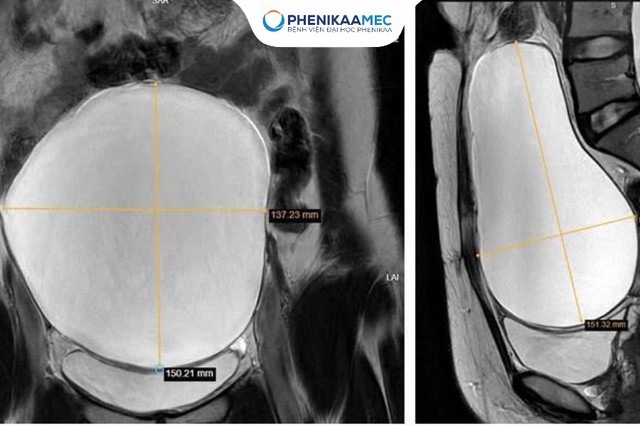

PhenikaaMec tiếp nhận trường hợp người bệnh H.T.H (36 tuổi, Hà Nội) trong tình trạng đau bụng kéo dài. Kết quả chụp cộng hưởng từ vùng chậu cho thấy một khối u nang buồng trứng trái kích thước 15,2 x 8,2 cm, chiếm gần trọn thể tích buồng trứng và hình thành trên nền sẹo mổ cũ hai lần trước đó. Đây là yếu tố khiến quá trình bóc tách khối u tiềm ẩn nhiều rủi ro, từ chảy máu, tổn thương phần phụ cho đến nguy cơ phải cắt bỏ buồng trứng nếu không được xử trí đúng kỹ thuật.

Hình ảnh cộng hưởng từ cho thấy khối u buồng trứng có kích thước lớn